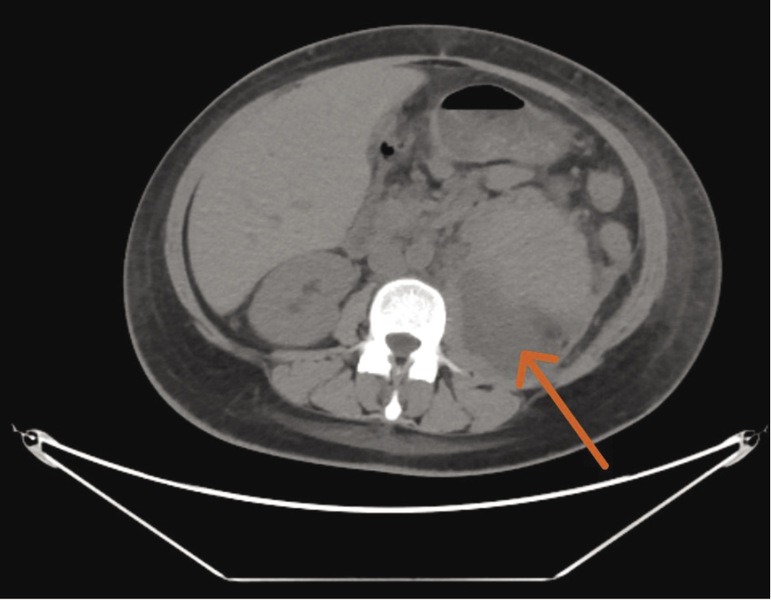

W efekcie działań prowadzonych w osiemnastej dobie leczenia stwierdzono stopniową normalizację parametrów nerkowych. W związku z utrzymującymi się wysokimi wartościami wykładników stanu zapalnego przeprowadzono kontrolną jednofazową TK jamy brzusznej, w której poniżej dolnego bieguna nerki lewej zaobserwowano obszar gęstopłynowy (79 × 68 × 89 mm) wychodzący z powiększonego lewego mięśnia lędźwiowego większego, przylegający do dolnej i przyśrodkowej części nerki (ryc. 5). Pacjentkę ponownie skonsultowano urologicznie i zakwalifikowano do drenażu patologicznego zbiornika płynowego. W wyniku nakłucia obszaru gęstopłynowego uzyskano wypływ 300 ml treści ropnej. W kontrolnej TK przeprowadzonej po drenażu nie stwierdzono obecności patologicznych zbiorników płynowych.

Rycina 5. Obraz jednofazowej tomografii komputerowej – badanie przeprowadzone w osiemnastej dobie hospitalizacji